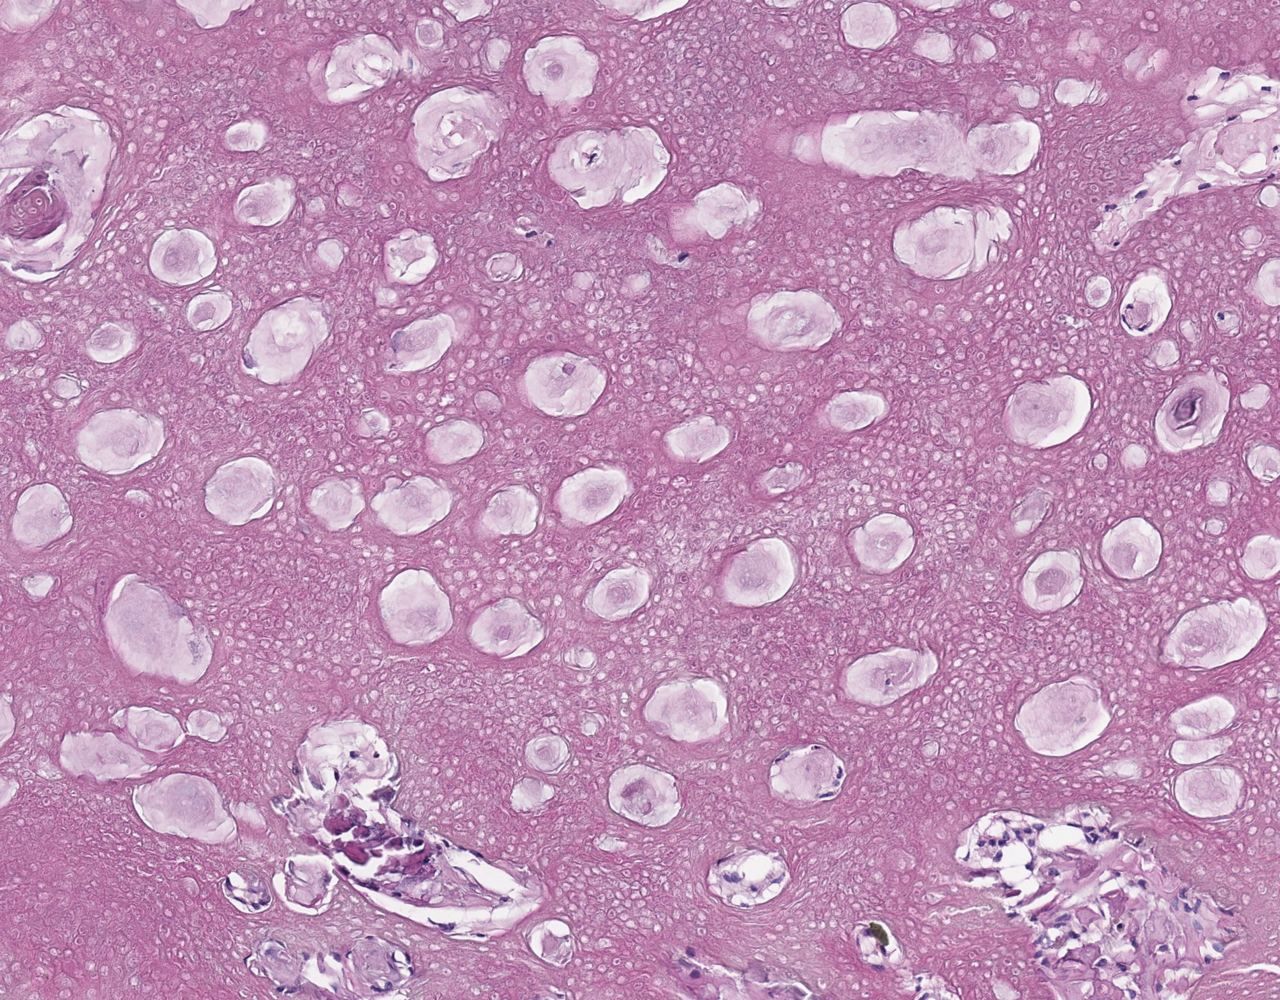

Базально - клеточная опухоль